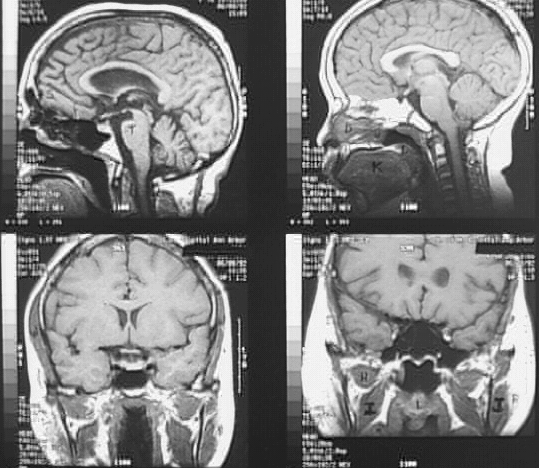

Radiology Images

Head & Neck: Head MRI 4 Frames: